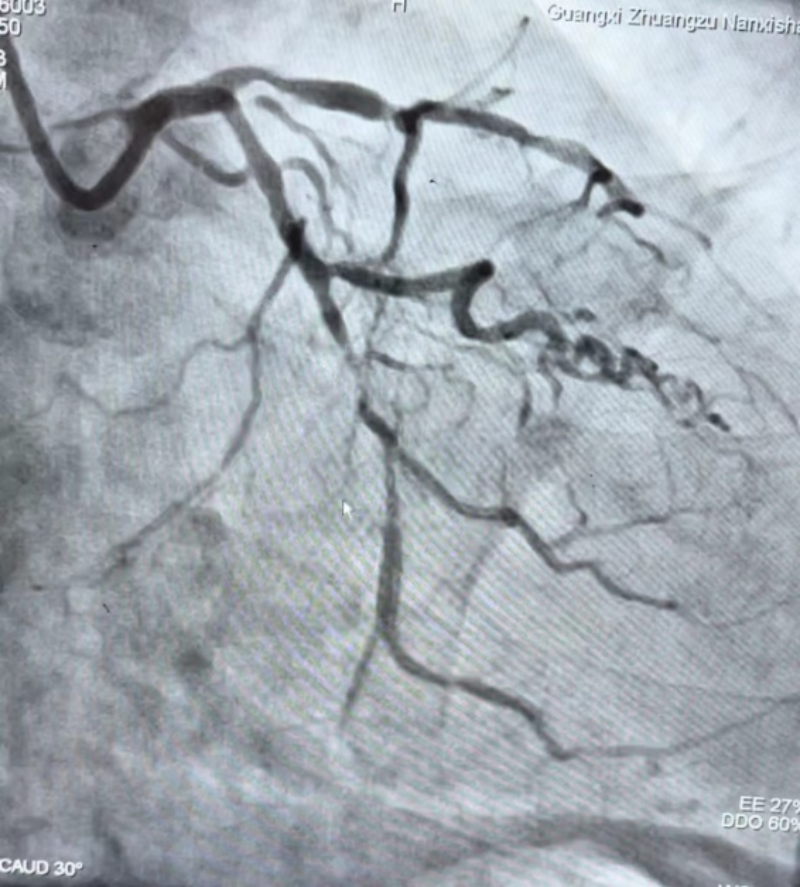

在进行充分的术前准备后,朱博士先将导丝顺利通过回旋支远段病变,再运用0.9mm的激光导管,采用准分子激光高功率高频率对斑块进行反复消融,最终成功通过激光导管,经过小球囊反复扩张后,成功植入支架,血流完全恢复。

3.术后影像。医院供图